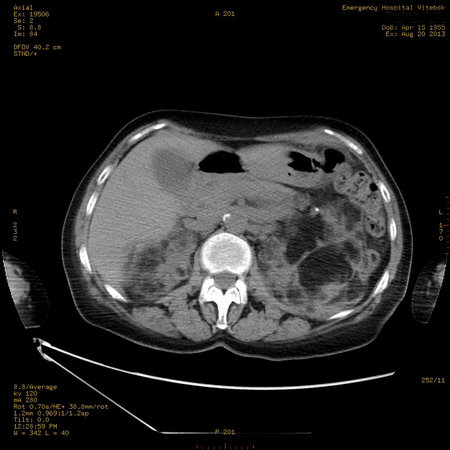

УЗИ почек - туберозный склероз

Пожилая женщина с нормальными мочевиной и креатинином.

Ангиомиолипоматоз почек , думаю компонент туберозного склероза.

Да, туберозный склероз.

Случай консультирован на кафедре радиологии Католического университета г.Лёвен (Бельгия) - зав каф. профессор Р.Оуен.